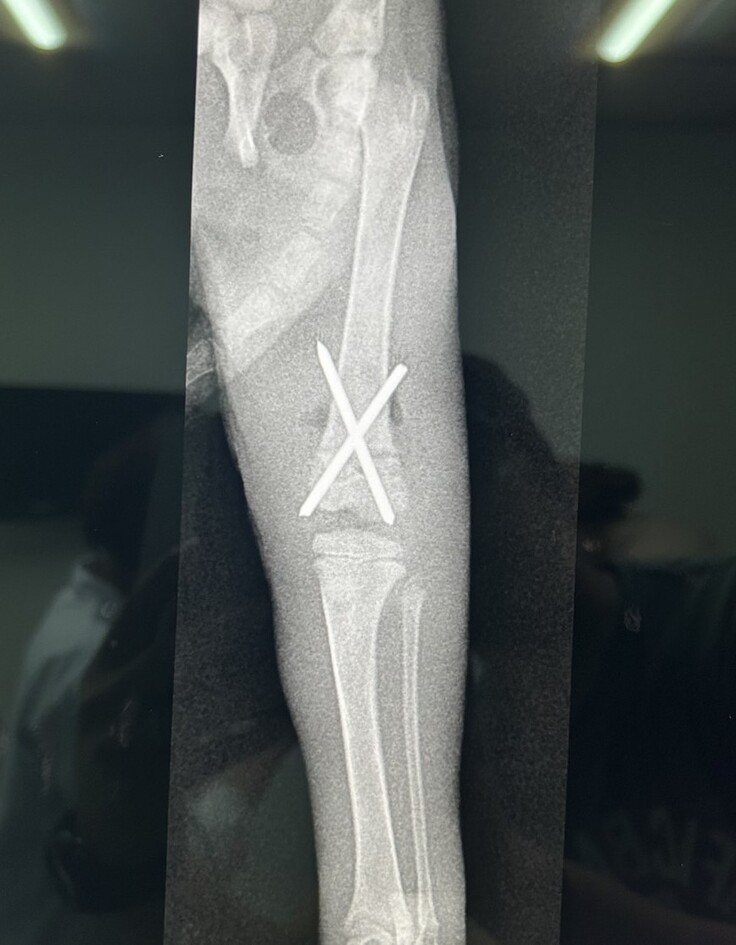

↓骨折部のレントゲン写真

・左脚の太ももの骨が写真の通り折れていました。

X線検査の結果、左側大腿骨遠位成長板骨折である事がわかりましたが、かかりつけ医では子猫の骨折の位置や状態が悪いので手術ができないという事で、手術を専門としていて信頼できる病院を紹介していただきました。